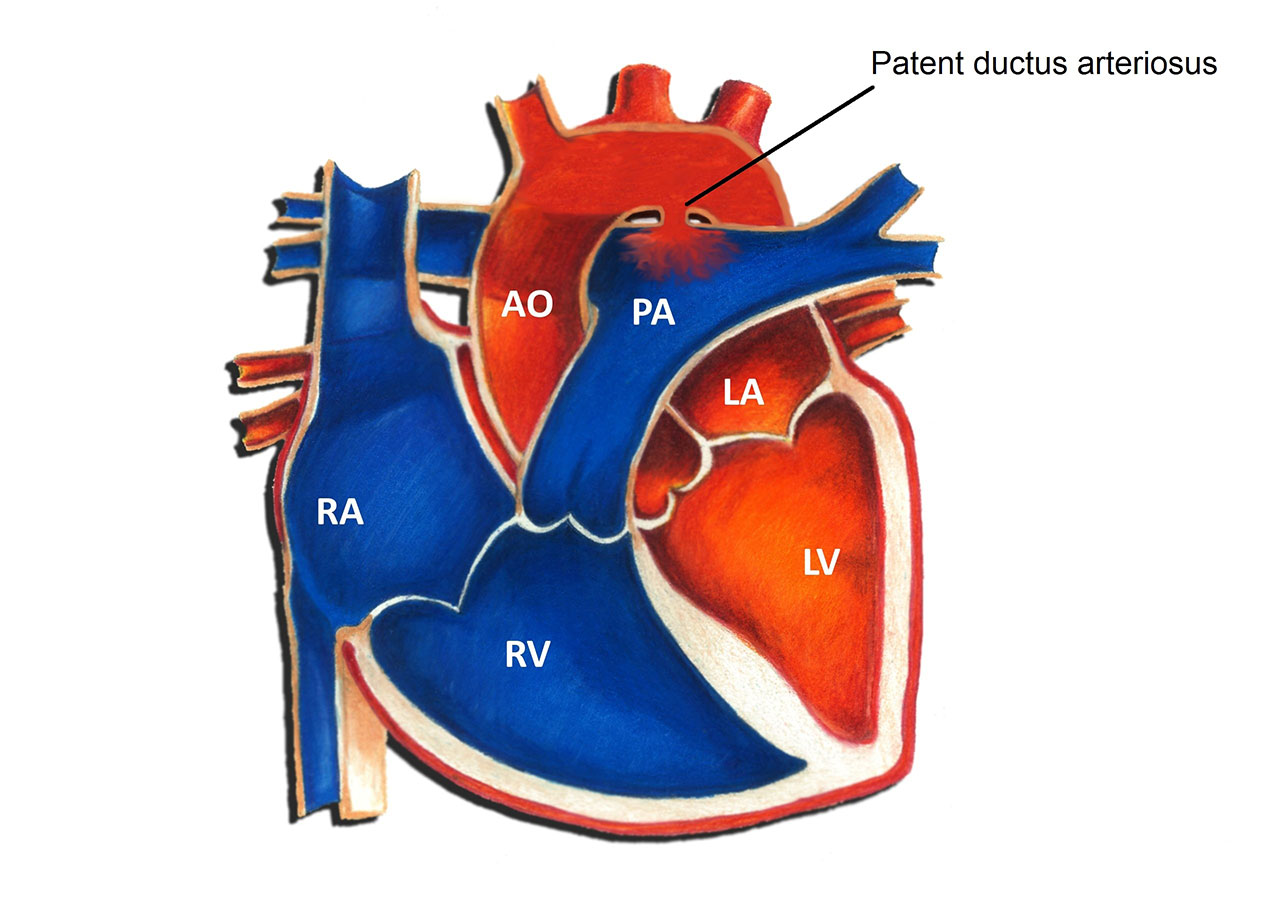

PDA Pathophysiology and Anatomy

Morphology of the PDA in premature infants The PDA resembles a hockey

Text Patent Ductus Arteriosus PDA in Premature Infants

PATENT DUCTUS ARTERIOSUS PDA IN CHILDREN Dr Gaurav Agrawal

Patent Ductus Arteriosus PDA in the newborn

PDA morphology and size are extremely variable in premature babies